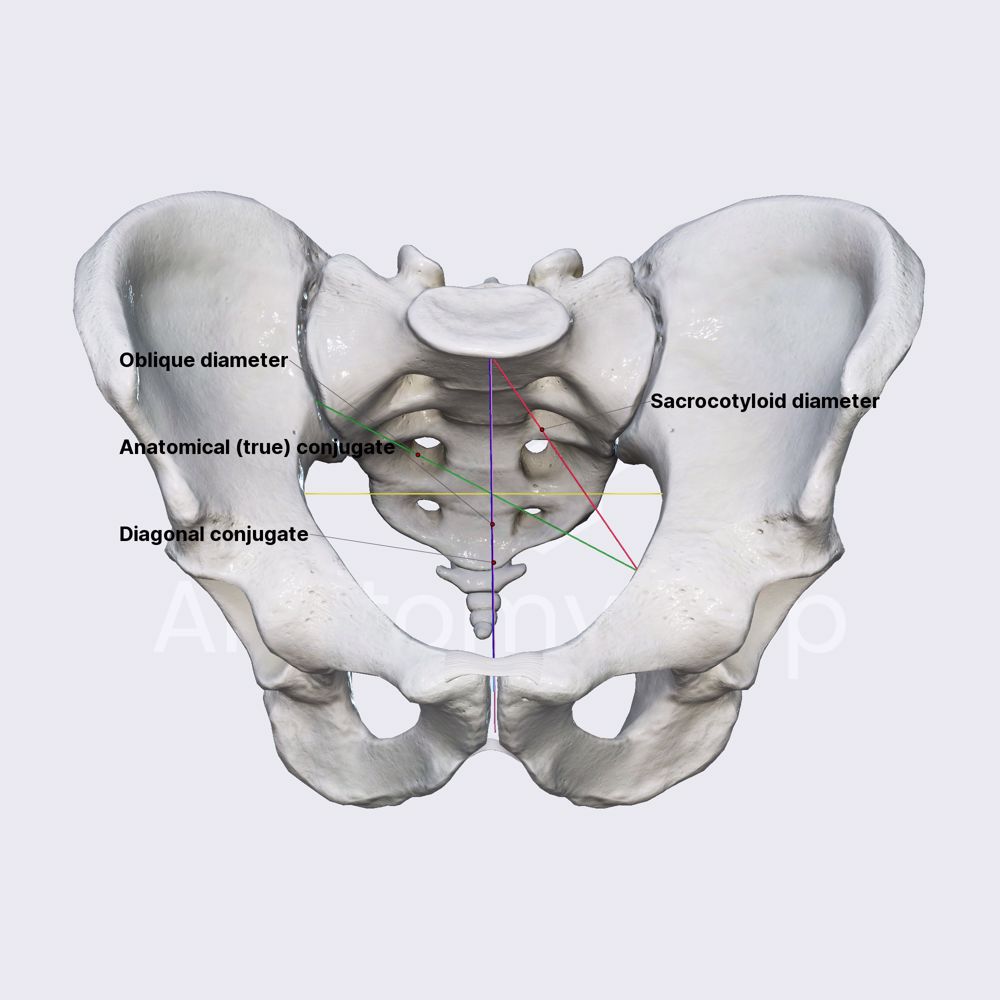

- Pelvic inlet diameters